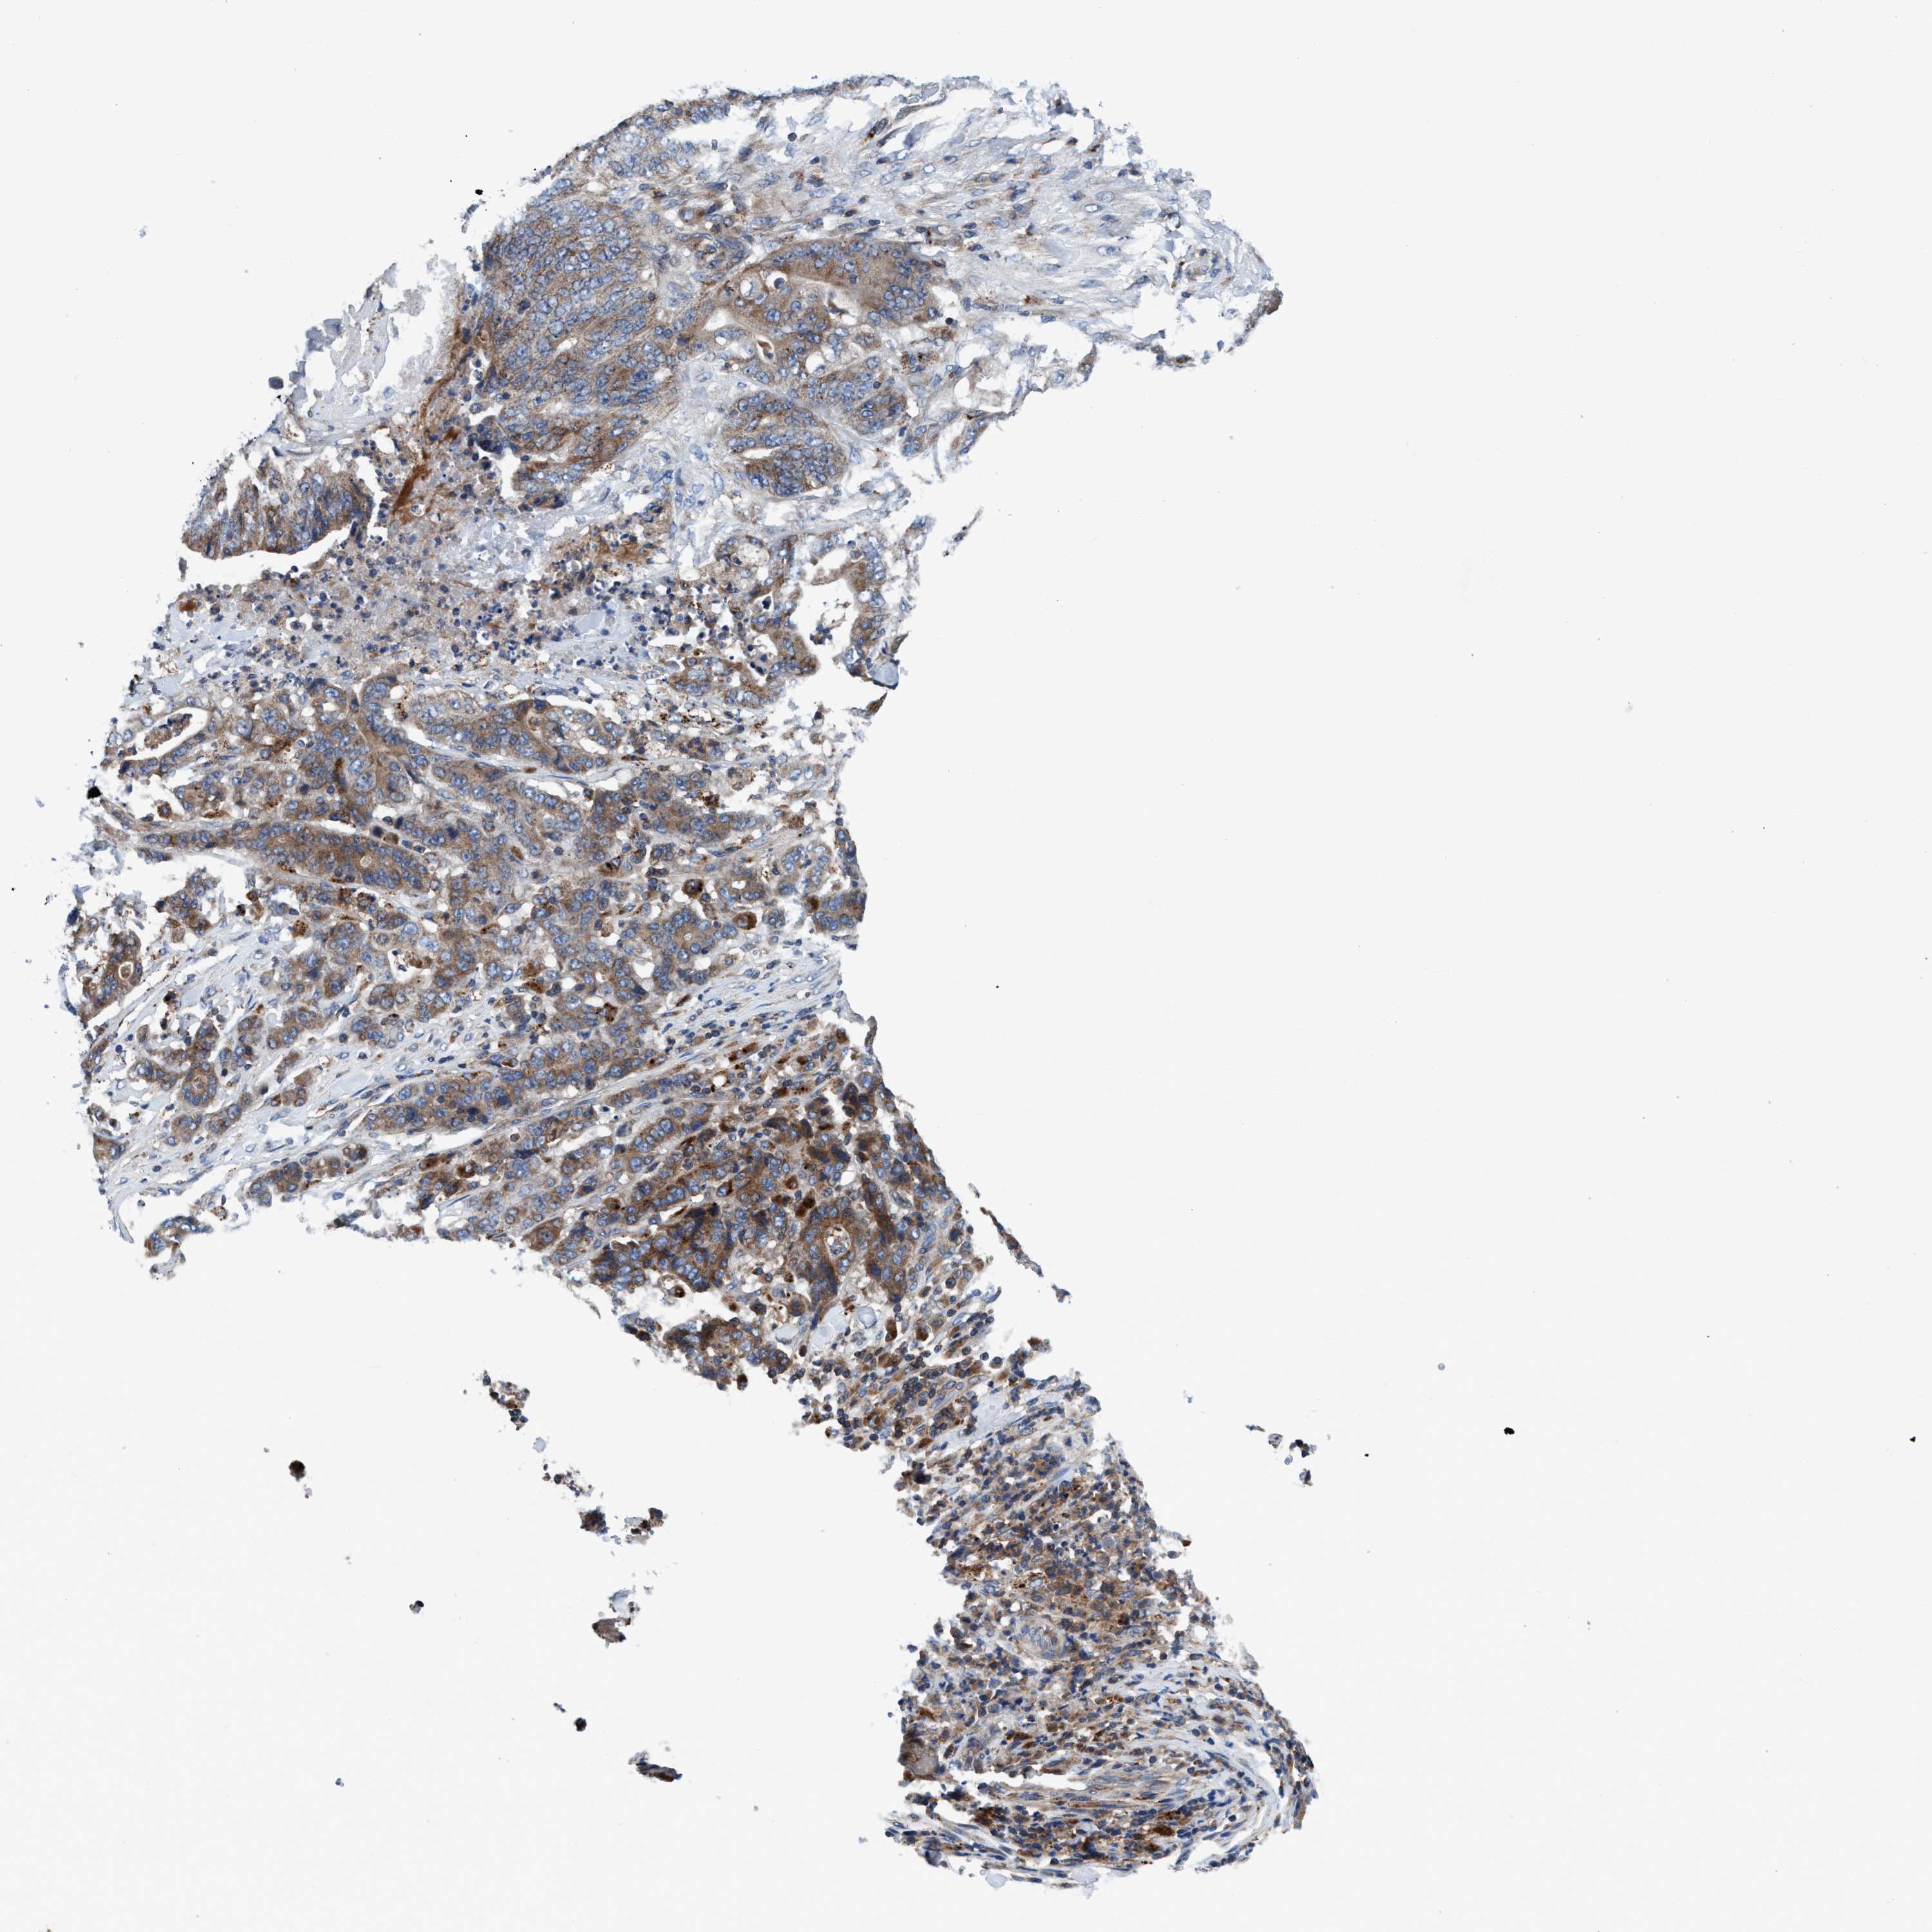

STOMACH CANCER - Protein expressioni

A mouse-over function shows sample information and annotation data. Click on an image to view it in a full screen mode. Samples can be filtered based on level of antibody staining by selecting one or several of the following categories: high, medium, low and not detected. The assay and annotation is described here.

Note that samples used for immunohistochemistry by the Human Protein Atlas do not correspond to samples in the TCGA dataset.

Antibody stainingi

Antibody staining in the annotated cell types in the current human tissue is reported as not detected, low, medium, or high, based on conventional immunohistochemistry profiling in selected tissues. This score is based on the combination of the staining intensity and fraction of stained cells.

Each image is clickable and will lead to virtual microscopy that enables deeper exploration of all samples and also displays staining intensity scores, fraction scores and subcellular localization as well as patient and tissue information for each sample.

Antibody HPA021335

Antibody HPA021830

Staining

High

Medium

Low

Not detected

Intensity

Strong

Moderate

Weak

Negative

Quantity

>75%

75%-25%

<25%

None

Location

Nuclear

Cytoplasmic/membranous

Cytoplasmic/membranous,nuclear

Adenocarcinoma, NOS